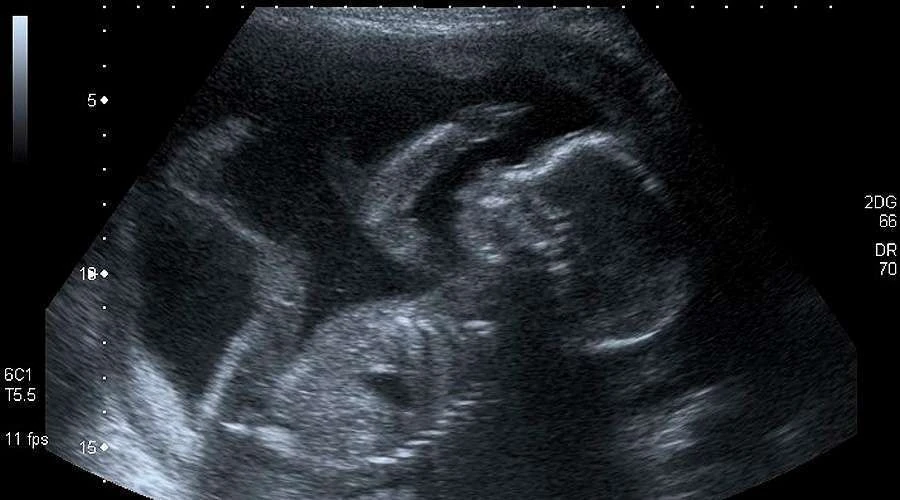

7.- Manipula los resultados de las ecografías

“Se deberá explicar a la usuaria su derecho a solicitar no ver las imágenes ni escuchar los sonidos. En caso de realizarse la ecografía, solo se compartirán con la persona la imagen o el sonido de los latidos si ella lo solicita expresamente. Si no lo hace, es de suma importancia tomar los recaudos necesarios para que aquello no suceda”, describe el protocolo en la página 38.

“A su vez, si es posible, facilitar distintas áreas donde se puedan evaluar separadas aquellas mujeres que buscan una interrupción de aquellas que reciben cuidados prenatales”, agrega.